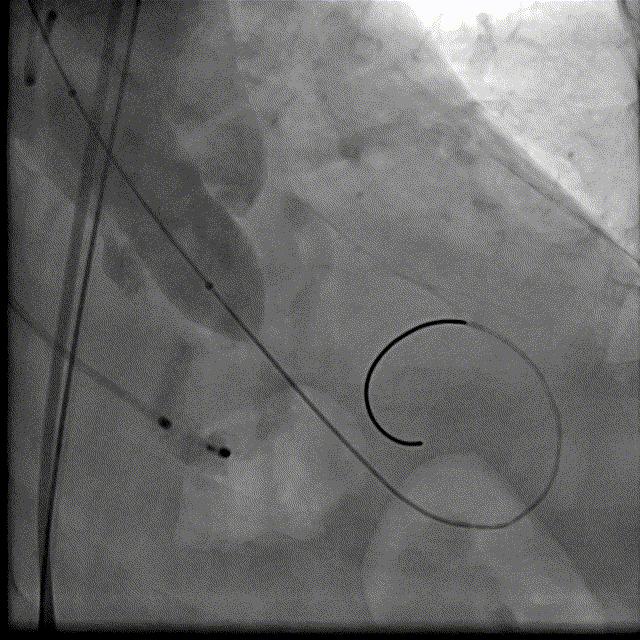

18球囊预扩DSA